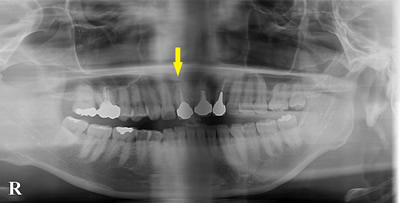

患者様の治療前のレントゲン写真です。写真の黄色矢印部の歯の周囲は、重度の歯周病で大きく歯槽骨が吸収されてしまっていました。そのため、写真の、赤色矢印で示す、下顎骨の中を通る神経までの距離がなく、インプラント埋入には、骨の高さが不足していました。

患者様の治療前のレントゲン写真です。写真の黄色矢印部の歯の周囲は、重度の歯周病で大きく歯槽骨が吸収されてしまっていました。そのため、写真の、赤色矢印で示す、下顎骨の中を通る神経までの距離がなく、インプラント埋入には、骨の高さが不足していました。